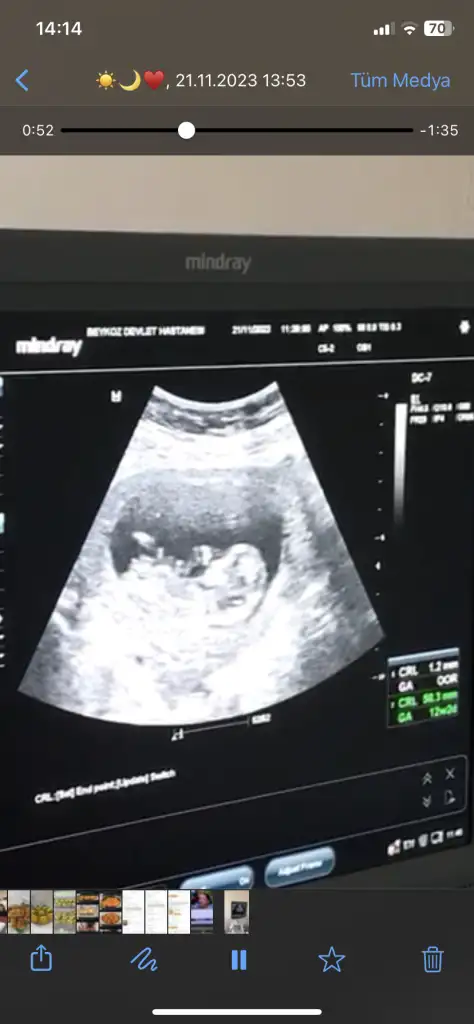

Benimkine de bakabilir misiniz doktorum 11+5te kız dedi 13+6da erkek dedi

İlk 3 fotoğraf 13+6

Son 2 fotoğraf 11+5